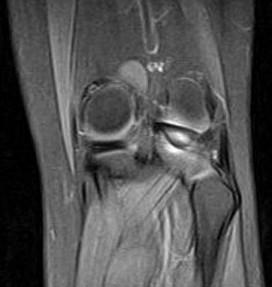

问题 男,16岁,左膝关节有过外伤,现肿痛,有膝关节弹响,请结合MRI检查,选出最可能的诊断 ( )

选项 A、关节结核 B、风湿关节炎 C、滑膜炎 D、半月板撕裂 E、化脓性关节炎

答案 D